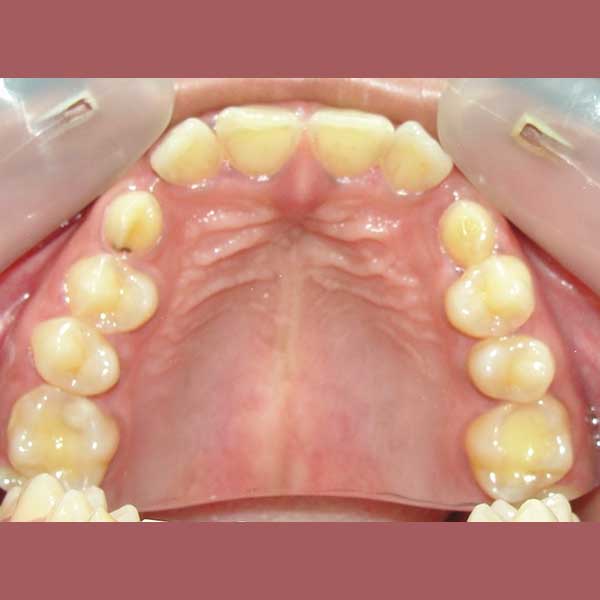

راجعتني هذه السيدة وهي تعاني من مشاكل معقدة؛ فأنيابها العلوية الدائمة لم تبزغ أبداً، وبقيت الأنياب اللبنية في مكانها. بالإضافة إلى ذلك، كانت أنيابها السفلية بازغة للداخل، مما سبب لها صعوبات كبيرة في الأكل والنطق وأفقدها الثقة بابتسامتها لدرجة أنها رفضت تصويرها في البداية.

بعد الفحص وأخذ الصور الشعاعية، أوضح الدكتور خالد الكاتب أن الأنياب العلوية موجودة ولكنها منطمرة بالكامل في عظم الفك، بالإضافة لوجود ضاحك سفلي منطمر أيضاً. وبسبب كبر سن المريضة، كان لا بد من خطة علاج متكاملة: